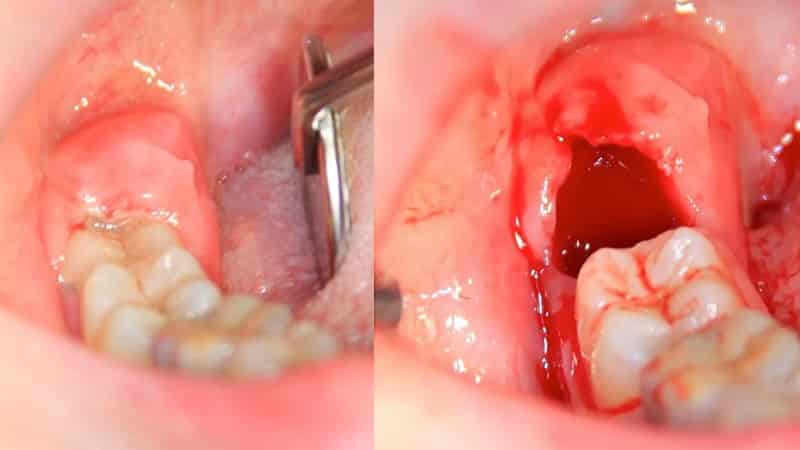

Особенности заживления десны

После проведения процедуры, опытный хирург должен пояснить пациенту, что десны могут болеть после удаления зуба в течение определенного времени. Сразу после операции, ямка заполняется кровью, а затем образуется защитный барьер из сгустка крови. Через день многие люди замечают, что их десны становятся желтыми. Это связано с возникновением налета на поверхности десны после удаления зуба. Но не стоит беспокоиться, так как через несколько дней этот сгусток превращается в слизистую часть, и рана полностью заживает, что приводит к снятию боли.